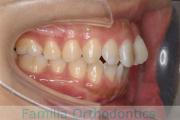

歯並びを治したいということで来院されました。下あごがやや右側に偏位して後退している、上顎前突(出っ歯)でした。上下左右から小臼歯を抜歯して、歯科矯正用アンカースクリューを併用したマルチブラケット法にて治療を行いました。約2年、24回の来院をしていただきました。

下顎の後退はいびきなどの上部気道の障害が出やすいと考えられます。

- ≫治療前

-

上顎

下顎

前歯の関係など

右側

正面

左側